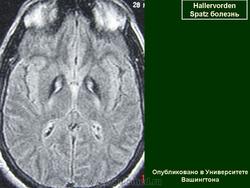

Галлервордена - Шпатца болезнь (J. Hallervorden, 1882-1965, нем. невропатолог; H. Spatz, совр. нем. невропатолог; син. ригидность прогрессирующая) - наследственная болезнь, связанная с нарушением обмена железа и липидов, проявляющаяся в возрасте 7-9 лет повышением мышечного тонуса, гиперкинезами, прогрессирующей деменцией, снижением зрения и пигментным ретинитом; наследуется по аутосомно-рецессивному типу.

Болезнь Галлервордена - Шпатца - наследственное заболевание экстрапирамидной системы, связанная с нарушением обмена железа и липидов и повреждением бледного шара и черной субстанции. Тип наследования аутосомно-рецессивный. При патоморфологическом исследовании характерным признаком является гиперпигментация бледного шара и черной субстанции. Обнаруживается пигментация коры полушарий большого мозга и таламуса. Пигмент находится внутри невронов и глиальных клеток, расположенных около сосудов; содержит железо (вместе с тем каких-либо нарушений обмена железа в организме не обнаружено). Наблюдаются утолщение и фрагментация аксонцилиндров в пораженных областях. Постепенно наступает дегенерация невронов коры полушарий большого мозга и мозжечка. Характеризуются нарастающей экстрапирамидной ригидностью, гиперкинезами (атетоз, торсионная дистония), затем развивается акинетико-ригидный синдром, пирамидная микросимптоматика, снижение интеллекта. Течение медленно прогрессирующее на протяжении 10 - 20 лет.

"Глаз тигра"-наглядно и красиво.

Вы правы. Выставил еще более нагладные исллюстрации.